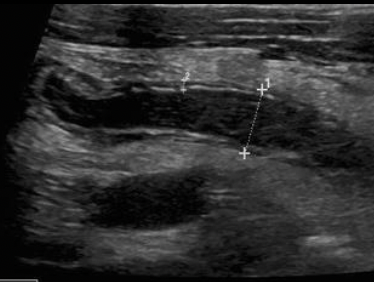

MEJOR MÉTODO DX NIÑOS

USG MAYOR 6 MM

EN DEDO DE GUANTE O SIGNO DE DIANA

DEDO EN GUANTE